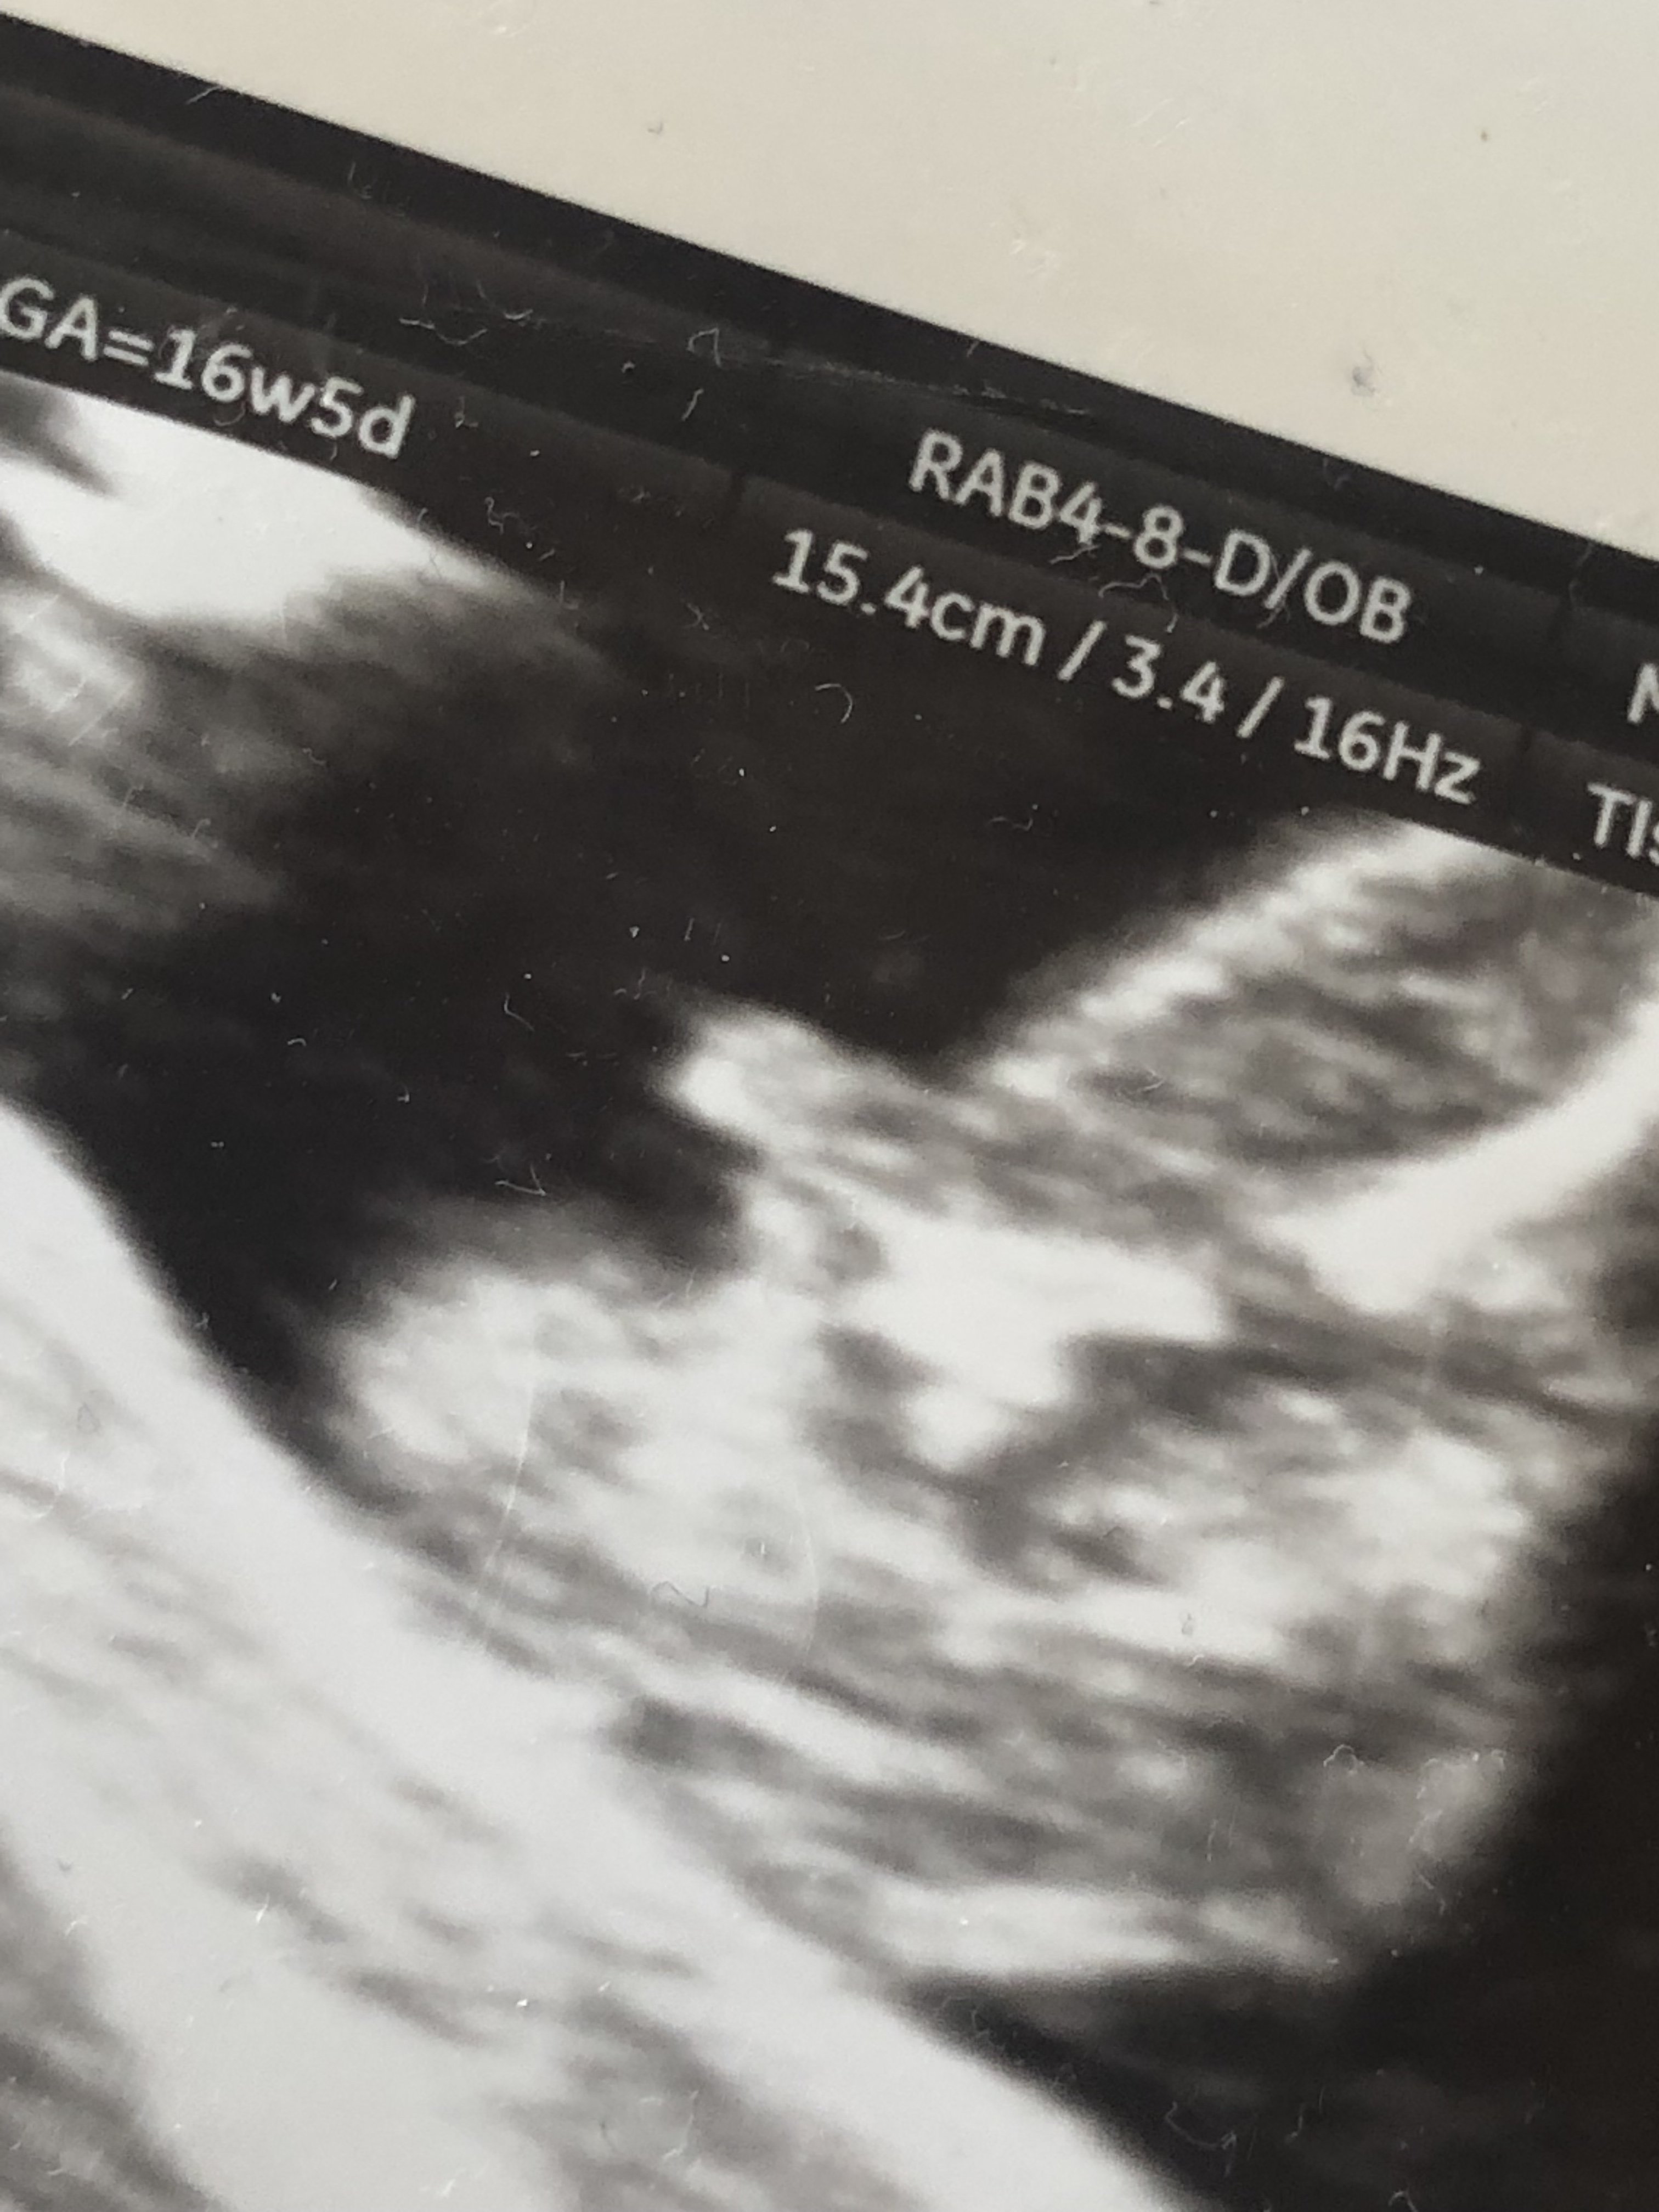

I teraz już wiem ze nie mam mieć co złudzeń, widzę trzy linie określające łechtaczkę i wargi sromowe, ale wiecie co ? Po zdjęciu z 16+5 powiedziano mi ze chłopiec i uwierzyłam i cieszyłam się jak głupia

Wiec już nie wierze, nie wierze w lekarza, w badanie w nieomylność.

• BCAF023E-7B75-4C28-96BB-8DCA9017C581.jpeg

BCAF023E-7B75-4C28-96BB-8DCA9017C581.jpeg

719,7 KB · Wyświetleń: 526